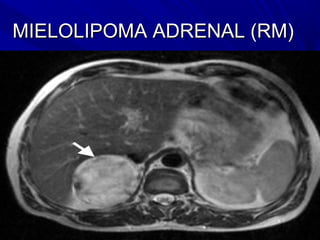

MIELOLIPOMA ADRENAL (RM)

Densidad compatible con tejido graso